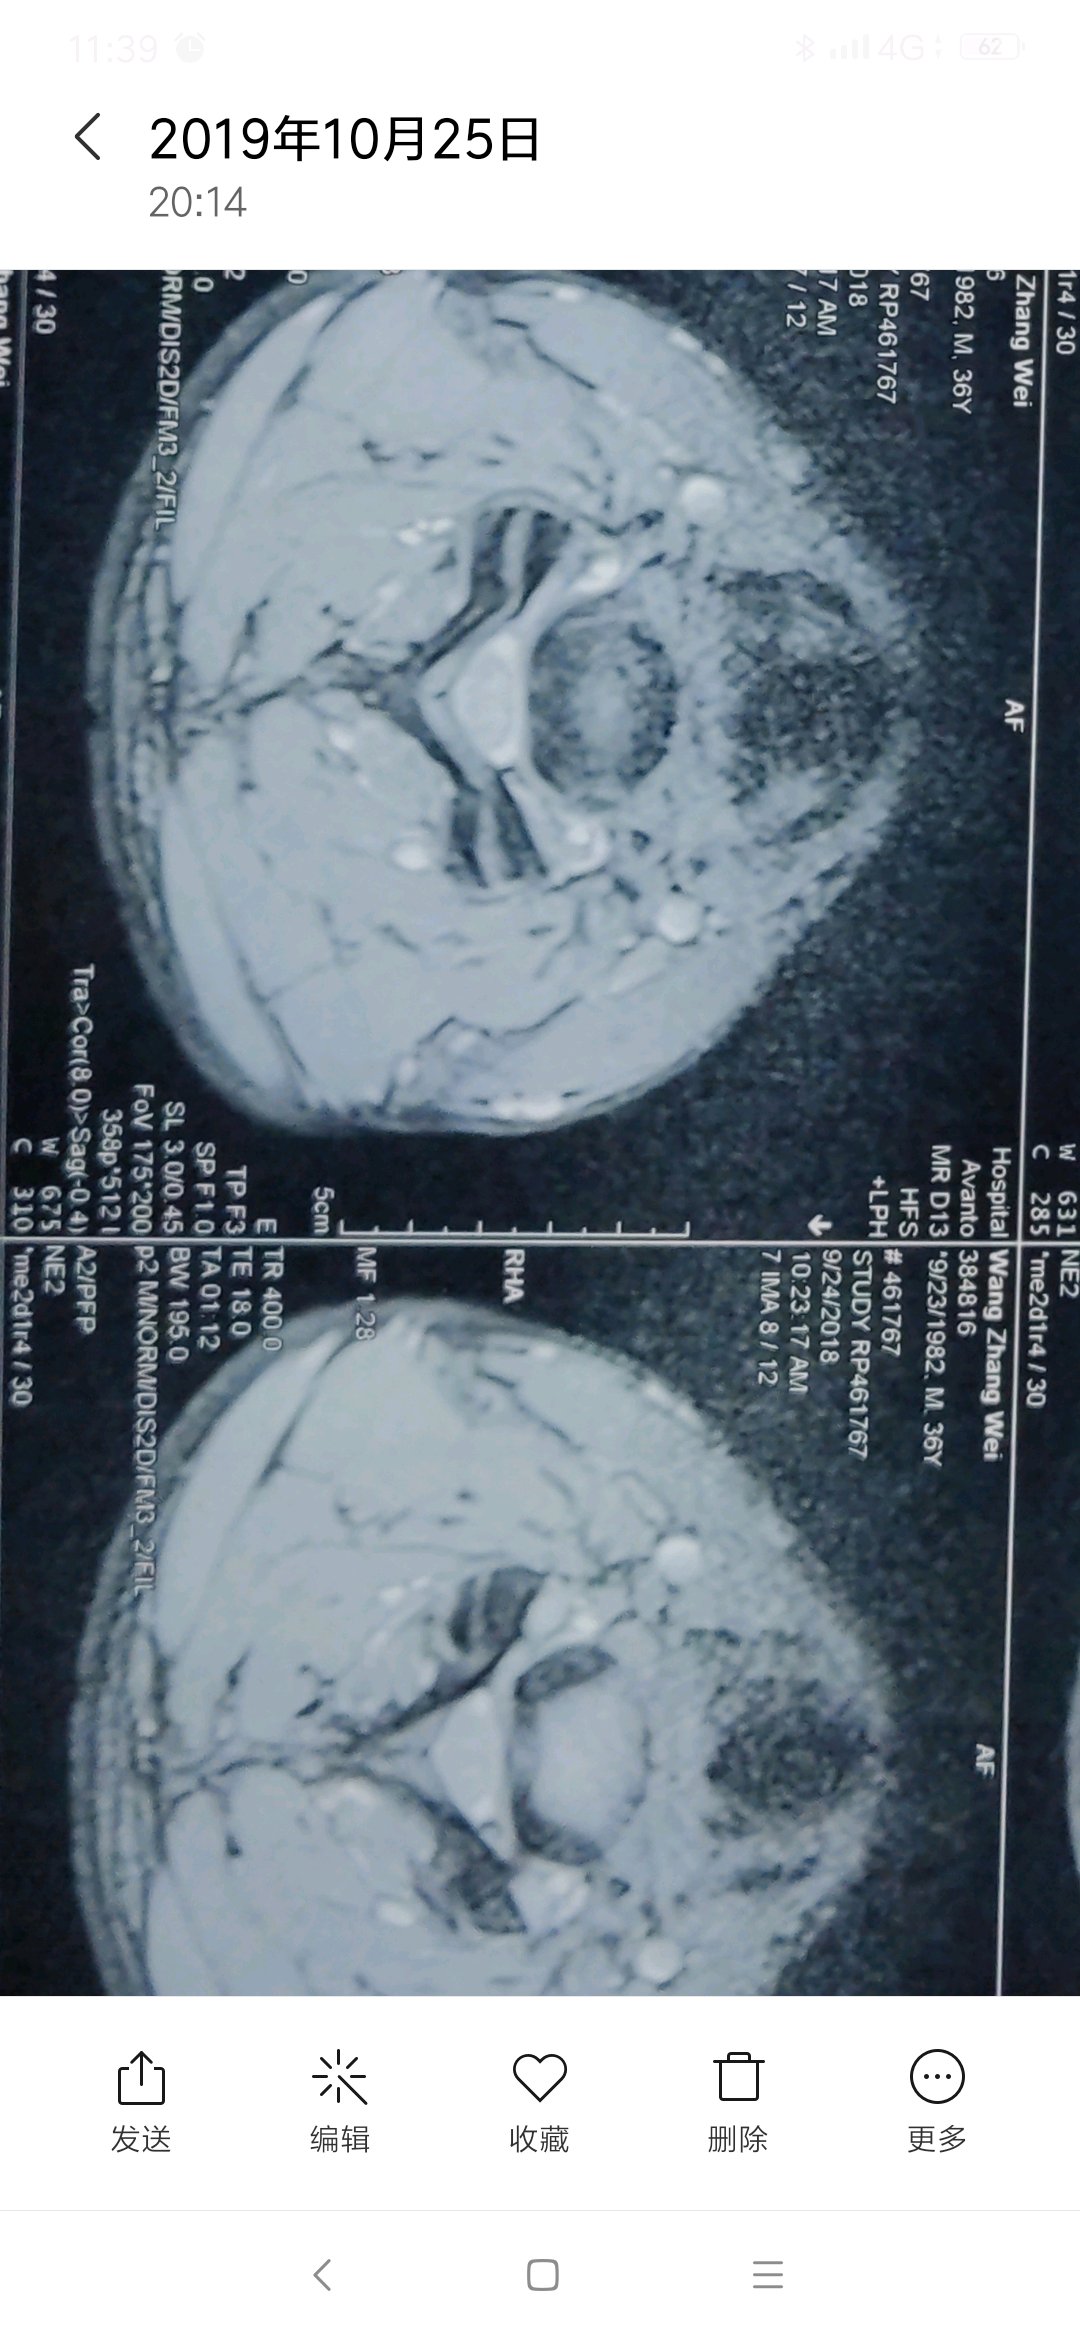

有专家吗,这个层度严重吗,怎么能治好,主要表现脖子疼痛,活动受限。

首先活动受限是扭头,低头仰头都受限?还是某个方向?

转头,抬头,低头,都会痛,疼痛主要在右侧

片子不严重,多锻炼就好了

每次去医院看病,医院都说不严重,可是痛起来真的太痛苦了。